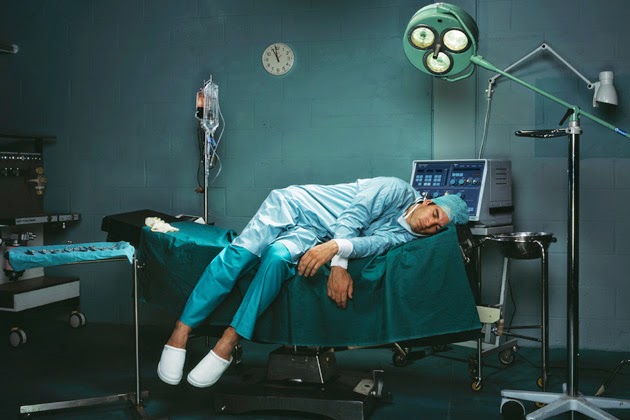

Prevalência de Burnout entre Cirurgiões Pediátricos: Revisão Sistemática e Metanálise